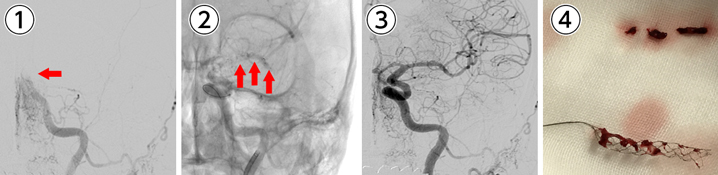

脳動脈瘤コイル塞栓術を施行。

①脳底動脈に長径10㎜の動脈瘤を認める(矢印)。

②カテーテル(細い管)から動脈瘤にコイル(細い金属)を挿入する(矢印)。

③動脈瘤に血液が流れ込まないように動脈瘤内にコイルを挿入。

④動脈瘤内に血液が流れ込まないようにして、再度動脈瘤から出血をすることを予防する。